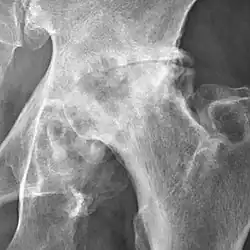

Osteoarthritis of the hip joint may also be graded by Tönnis classification. There is no consensus whether it is more or less reliable than the Kellgren-Lawrence system.[8]

Severe (Tönnis grade 3) osteoarthritis of the hip.

Tönnis classification[9]

Grade Description

3 Severe:

• large bone cysts

• severe joint space narrowing, or joint space obliteration

• severe deformity of the head